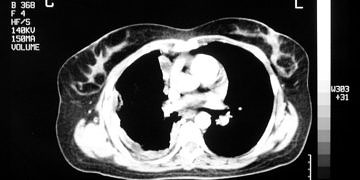

Devamıİntraplevral hava birikmesi ve buna sekonder gelişen akciğer kollapsıdır. Mekanizma; alveolle plevral aralık arasında ilişki, atmosferle plevral aralık arasında ilişki, plevral aralıkta gaz üreten bakteri.